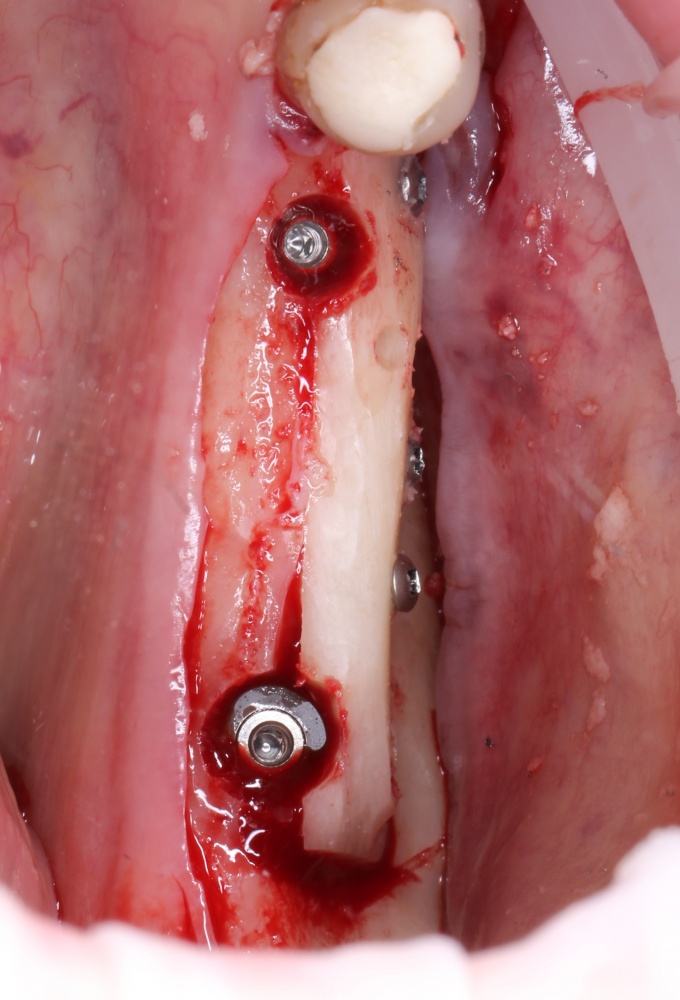

Первое и самое очевидное — для аутотрансплантации нужна донорская зона. Это увеличивает масштаб хирургического вмешательства и повышает его травматичность:

Забор костного фрагмента проводится с наружной косой линии с помощью ультразвукового пьезохирургического инструмента. Ничего сверхнового и супернеобычного тут нет, совершенно стандартная методика. С той лишь разницей, что молоток для этого используют только фашисты и только в гестапо использовать не нужно, всё делается усилием и ловкостью рук.